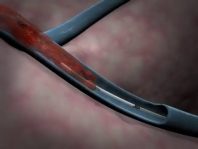

Trombektomi: Anjiyo yöntemiyle damardan girip trombektomi cihazıyla pıhtıları parçalayıp çıkartmaişlemiyle gerçekleştirilir.